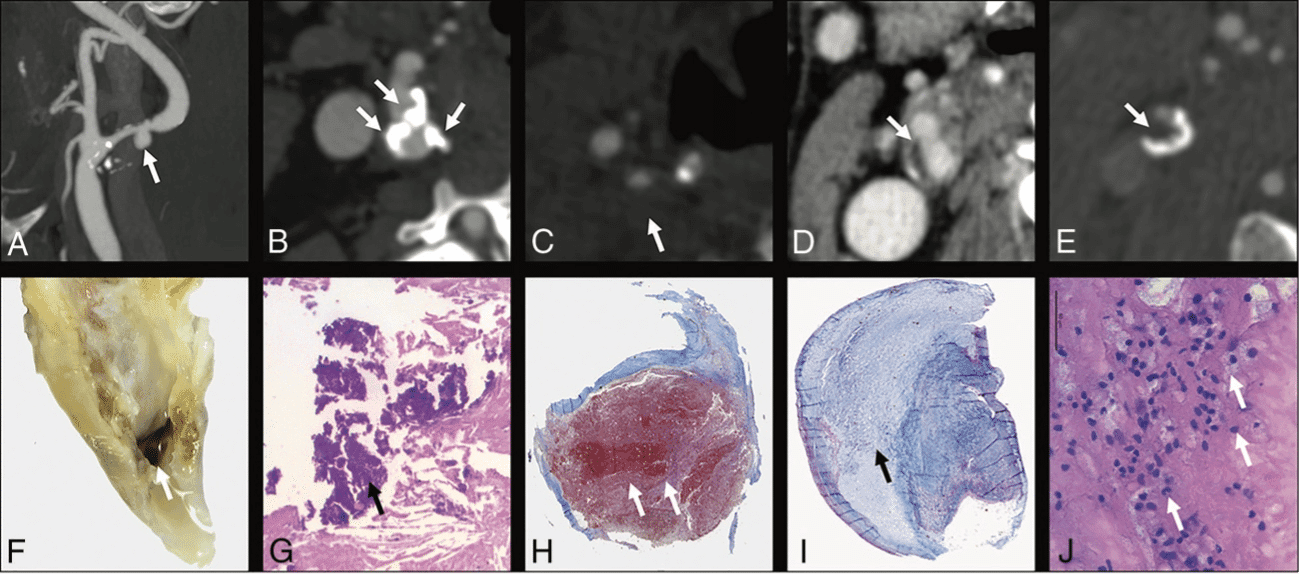

Como regra geral, estudos histopatológicos mostraram que as placas vulneráveis são caracterizadas por cápsula fibrosa afilada ou rota, erosões endoteliais, inflamação, núcleo lipídico / necrótico (“lipid-rich necrotic core” – LNRC), presença de neovascularização e hemorragia intraplaca, destacando-se que a posição do LNRC e do afilamento da cápsula fibrosa estão intimamente ligados ao risco de rotura da placa. As placas estáveis e assintomáticas tipicamente contêm mais tecido fibrótico e calcificações.

As características que definem a vulnerabilidade da placa estão relacionadas à ocorrência de eventos isquêmicos independentemente do grau de estenose, tanto em pacientes sintomáticos quanto em assintomáticos. A presença de hemorragia intraplaca, por exemplo, foi associada a um aumento de seis vezes no risco de evento cardiovascular.

Vários estudos já demonstraram que as calcificações são um fator estabilizador da estenose carotídea, mais comum em pacientes assintomáticos que sintomáticos, associadas a menores índices de inflamação, acúmulo de macrófagos, neovascularização e hemorragia intraplaca, o que suporta seu uso como ferramenta de estratificação de risco por imagem.